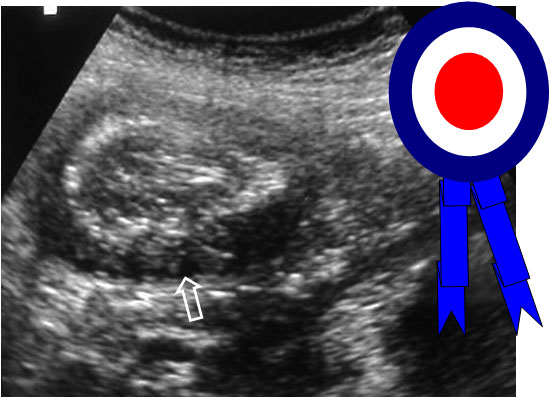

SIGNO DE LA ESCARAPELA

Signo de invaginación intestinal visible tanto en ecografía como en la TC abdominal, consistente en la imagen de bandas concéntricas de diferente ecogenicidad o densidad, correspondiente al asa invaginada en el interior de la invaginante, vista en un corte axial al asa. En ecografía, las bandas hiperecogénicas están formadas por la mucosa y la muscularis de la mucosa, y las hipoecogénicas corresponden a la submucosa.

En la literatura anglosajona, este signo es más frecuentemente descrito como Signo de la diana o Signo del donut.